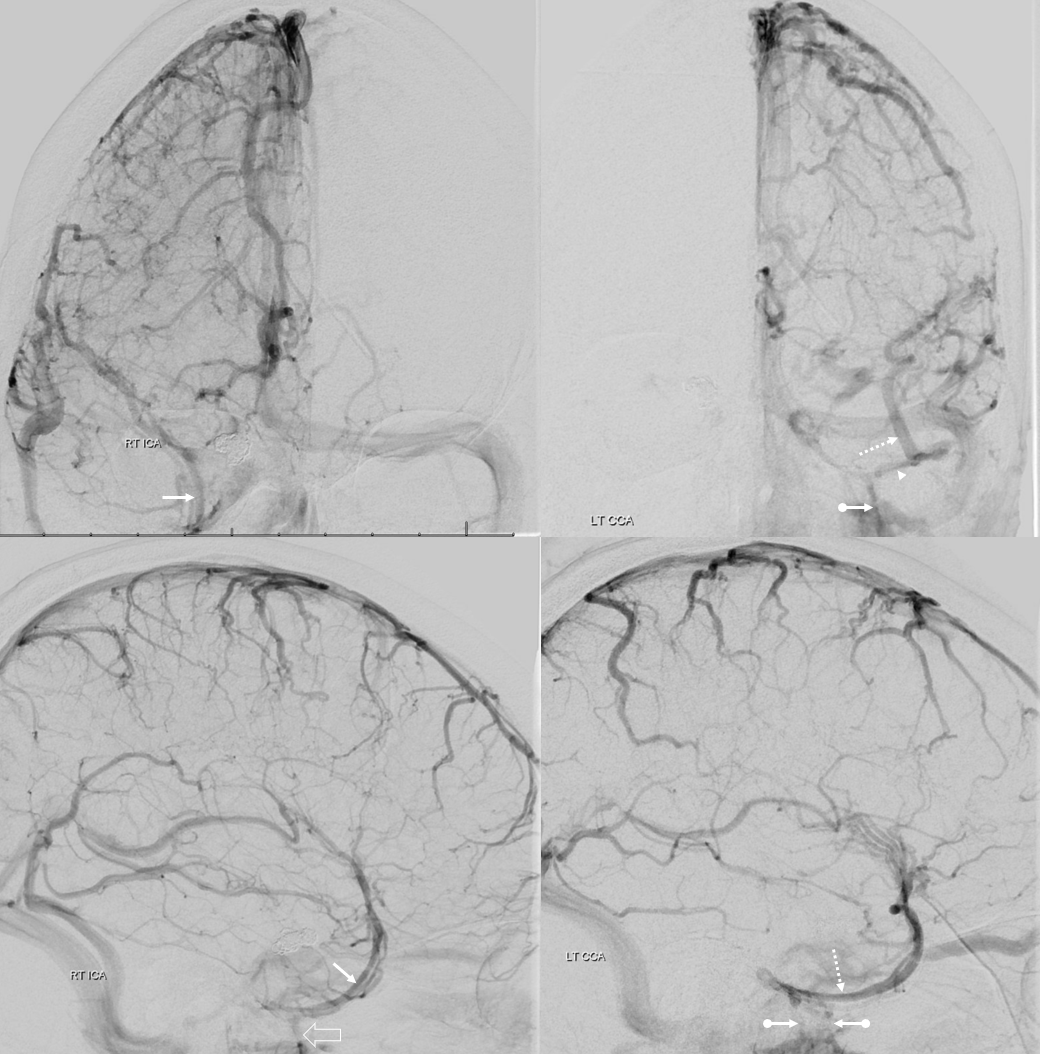

Below is a case of severe venous sinus thrombosis and secondary parenchymal venous infarcts

The explanation for the above tragic pattern is below. On the right, sigmoid and transverse sinuses are patent. However, the Labbe is hypoplastic, and majority of outflow used to go to the Trolard, into the now occluded SSS. There is no other effective way to go — the trolard tries to decompress via a left diploic vein, and convexity tries to access the deep venous system (which normally should not be well-seen in setting of hypoplastic right A1 segment). The left situation is much better, as well-developed superficial sylvian veins drain into the patent Cavernous Sinus. Thus, despite thrombosis of the left transverse and sigmoid sinuses, the left hemisphere is doing better, while the right one, which has patent transverse and sigmoid sinuses, is devastated.

Post venous thrombectomy — with limited results. Note presence of same left diploic vein as seen in right ICA injection, and connection between the distal superior sagittal sinus and the deep venous system via the inferior sagittal sinus.

Sagittal Sinus Thrombosis — collaterals.

All of the above anatomic knowledge can become very useful in evaluation of venous thrombosis. Numerous collateral pathways develop in this setting attempting to compensate for the loss. The most dramatic cases usually involve the largest channel — the superior sagittal sinus. In this case, a man presented with what initially was thought to be vasculitis-related brain hemorrhage. Subsequent workup led to an angiogram, where sagittal sinus thrombosis with extensive trans-cerebral and trans-osseous emissary vein collateral channels was seen. In retrospect, these findings were present on the patient’s earlier contrast MRI. “Venovibe” or other contrast-enhanced MR venograms can very sensitive, particularly when interpreted with the appropriate index of suspicion. Noncontrast 2-D time of flight MRV I consider to be next to useless as a problem-solving technique. Any thin-slice postcontrast T1 study is vastly superior.